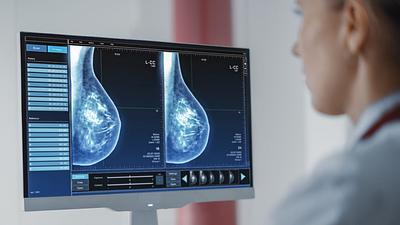

Modelo de inteligência artificial analisa mamografias para avaliar risco do desenvolvimento da doença. Técnica pode ajudar a identificar casos não detectados pelo exame tradicional.

A ferramenta de IA foi aplicada em tempo real e envolvendo um grupo ampliado de pessoas, em vez de ser utilizada posteriormente como vinha sendo feito até agora.

Os laudos dos exames de mamografia realizados no Centro Carioca de Diagnóstico e Tratamento por Imagem (CCDTI) são avaliados e assinados por profissionais médicos capacitados, no entanto, a IA auxilia na identificação de possíveis lesões difíceis de serem vistas.